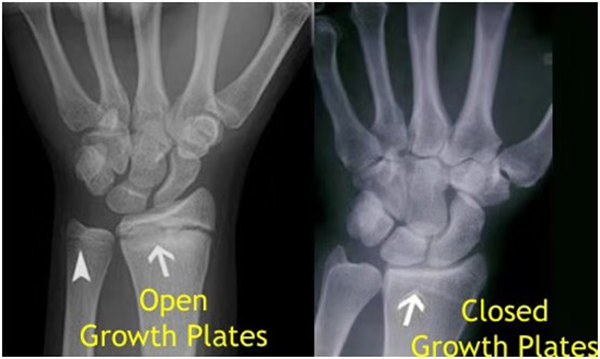

其實(shí)想要了解孩子的生長發(fā)育情況或者說孩子未來身高的趨勢,測骨齡是個好辦法。臨床上通常拍攝兒童的左手正位X光片 , 采用《中華-05》骨齡標(biāo)準(zhǔn)對手腕骨發(fā)育程度進(jìn)行骨齡評價。